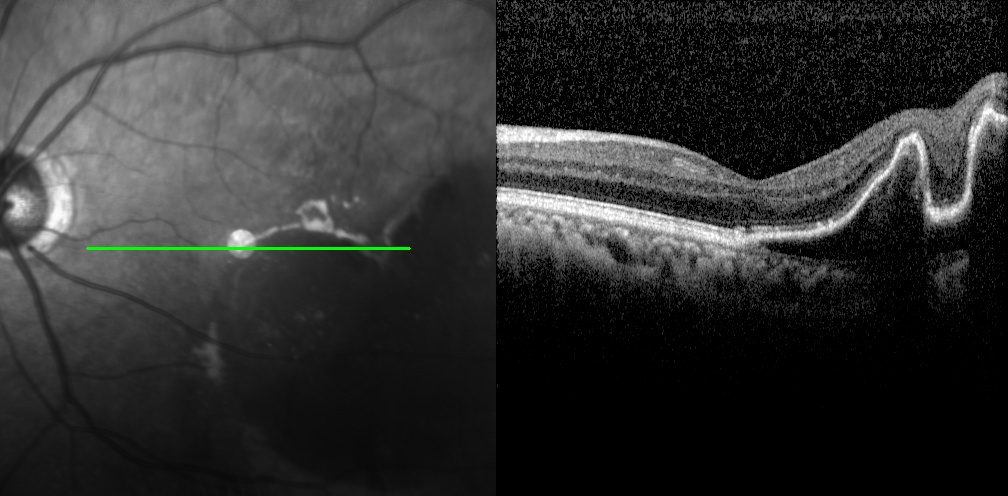

左眼調(diào)整用藥半個(gè)月后檢查圖片